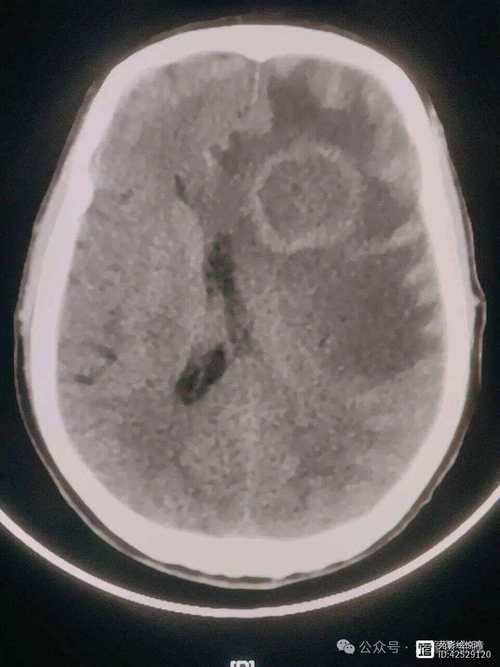

| 增强扫描 (T1WI + Gd) | 通常不强化,或出现脑回状、线状强化(代表血脑屏障破坏和侧支循环形成)。 | 环形强化是其典型表现,早期脓肿壁不均匀、厚薄不一;成熟后脓肿壁光滑、均匀、厚度一致。 |

急性期小结: 在超急性期(<6小时),DWI是诊断脑梗的金标准,而脑脓肿通常DWI也高信号。临床病史(突发 vs 渐进、有无发热) 和增强扫描的环形强化是鉴别关键,如果看到典型的环形强化,应高度怀疑脑脓肿。

| 增强扫描 (T1WI + Gd) | 囊壁可能不强化或仅有轻微线样强化,如果形成空洞脑膜瘤样强化(即囊壁和分隔都强化),则提示“囊性脑瘤”,需与囊性肿瘤鉴别。 | 典型的环形强化依然存在,如果脓肿壁非常光滑、均匀,且DWI中心高信号,基本可以确诊为脑脓肿。 |

慢性期小结: 当病变进入慢性期,DWI/ADC序列是区分脑梗液化坏死和脑脓肿的“照妖镜”。

- 脑梗液化: DWI低信号,ADC高信号。

- 脑脓肿: DWI高信号,ADC低信号。